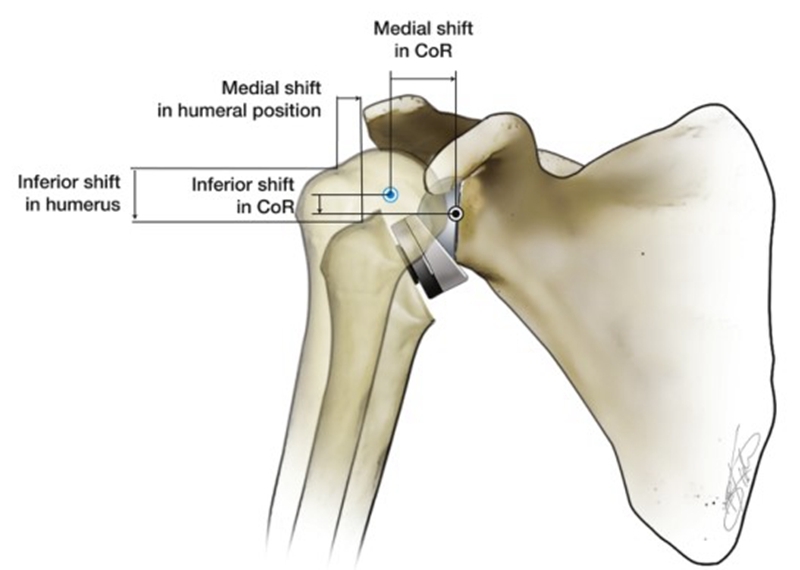

20世纪70年代初,为解决合并有严重肩袖功能障碍患者的肩关节置换,反式肩关节置换(Reverse total shoulder arthroplasty,RTSA)的概念首次由Neer提出,但因关节盂组件的早期失效,随后便将此概念放弃。1985年,Paul Grammont根据Neer提出的概念进行改良,将旋转中心向内侧和远端移动,改变了三角肌的力臂和张力,从而完美的解决了肩袖功能缺失的问题[2]。

反式肩关节假体的设计原理

反式肩关节置换术(RTSA)可翻转自然肩的解剖结构关系,以恢复肩关节的稳定性。RTSA通过使关节盂侧凸起,肱骨头侧凹陷,以此来创建一个支点和旋转中心(Center of rotation,CoR)。当三角肌收缩从而外展上臂时,该支点的生物力学作用便是防止肱骨头上移。RTSA特点便是让人工肩关节的旋转中心及肱骨头相对于自然肩的位置内移和下移,不同的RTSA假体设计有所不同,CoR分别下移5~10 mm及内移20~30 mm,肱骨头分别下移25~40 mm及内移5~20 mm[3][4]。

相对于人体自然的肩关节而言,内移CoR有一个显而易见的优点是三角肌的外展力矩臂从10mm增加到30mm,从而提高了三角肌的外展效率,更少的肌肉力量便可以产生相同的扭矩,而这一特点也让肱骨头的外展动作不再完全依赖于完整肩袖的下压功能[5]。